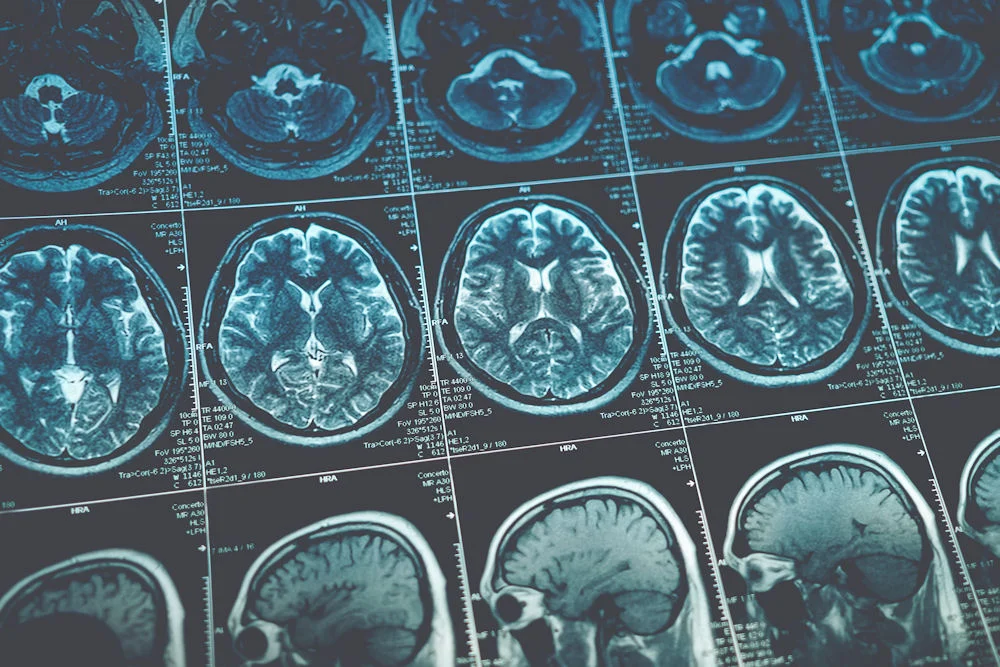

Research from the NIAAA shows that chronic alcohol exposure can cause brain cells to shrink and even die, particularly in regions responsible for learning, memory, and decision-making. Brain scans of long-term drinkers often show reduced volume in the frontal lobes and cerebellum.

According to a 2022 review in The Lancet, there is no “safe” level of alcohol consumption for brain health. However, risk increases substantially with heavy, prolonged use. Brain imaging studies show that even moderate drinkers (7-14 drinks per week) may experience some reduction in brain volume compared to non-drinkers.